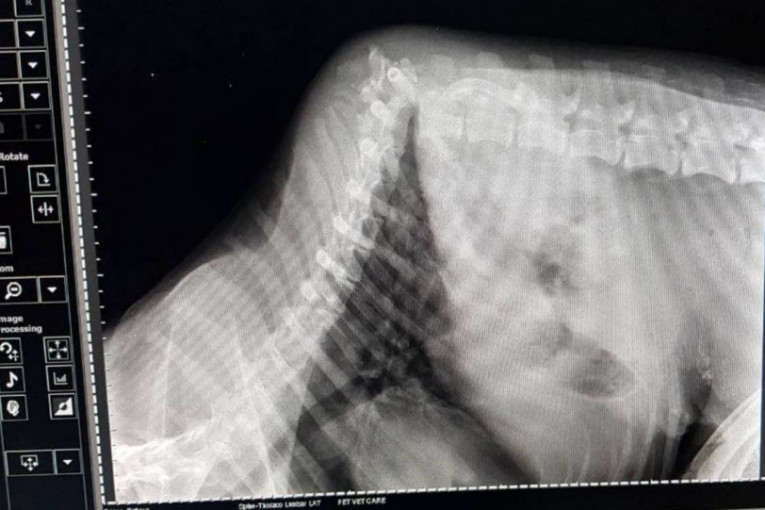

Kičma psa je slomljena i mora da se uradi operacija kako bi se ispravila i fiksirala. Troškovi za nedelju uveče su 15.000 dinara, a stacionar za ponedeljak 3000. Operacija će koštati 500 evra, danas bi trebalo da dođe do dogovora o terminu i moraju se platiti troškovi od juče i prekjuče.

Zvezdaninu objavu prenosimo u celosti kao i video snimak Leonove kičme na kojoj se nalaze crvi. Upozoravamo sve da snimci nisu nimalo prijatni.